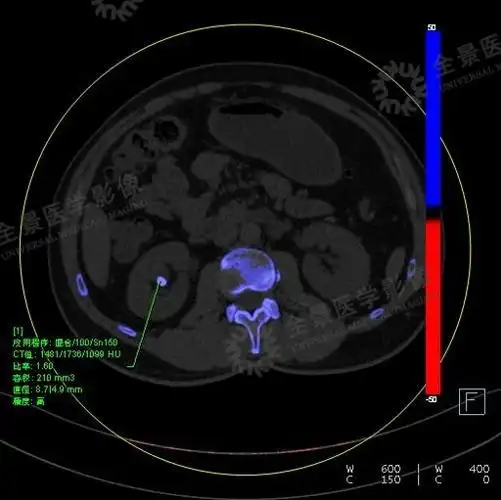

双能量ct可将尿酸结石和其他类型的肾结石区分开来:后处理结果会显示

【高尚病例】肾结石的双能量ct分析 - 知乎